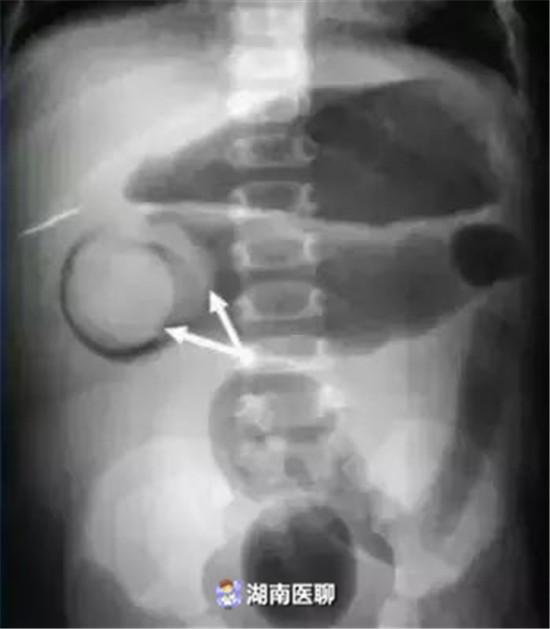

在儿外及放射科医生的紧密配合下,把空气灌入结肠,在X光机监视下,那段“躲”起来的肠子立刻显出了原型,这样总共不到30分钟就把“*猫猫躲**”的肠子给“揪”了出来。结束了“*猫猫躲**”的游戏后,小男孩很快就恢复了健康。

非手术治疗包括X线下空气灌肠、钡灌肠复位和超声监视下水压灌肠复位,其中以空气灌肠复位临床施行时间最早、范围最广,广受患儿家属所接受。

(空气灌肠中可见套叠肠管头部)

(套头达降结肠远端, 势必增加灌肠整复难度)